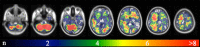

Methods: This monocentric retrospective study includes 369 untreated patients with 3313 intraaxial brain metastases. Following semi-manual segmentation of metastases on post-contrast T1WI, cumulative spatial probability distribution maps of brain metastases were created for the whole group and for all primary tumors. Furthermore, mixed effects logistic regression model analysis was performed to determine if the primary tumor, patient age, and patient sex influence lesion location.

Results: The cerebellum as location of brain metastases was proportionally overrepresented. Breast and pulmonary cancer caused higher number of brain metastases to what would normally be expected. Multivariate analyses revealed a significant accumulation of brain metastases from skin cancer in a frontal and from breast and gastrointestinal cancer in a cerebellar location.